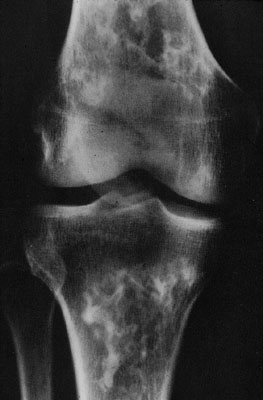

Bone infarct (aseptic necrosis)

X-ray of multiple infarcts of the tibia and femur in caisson disease.